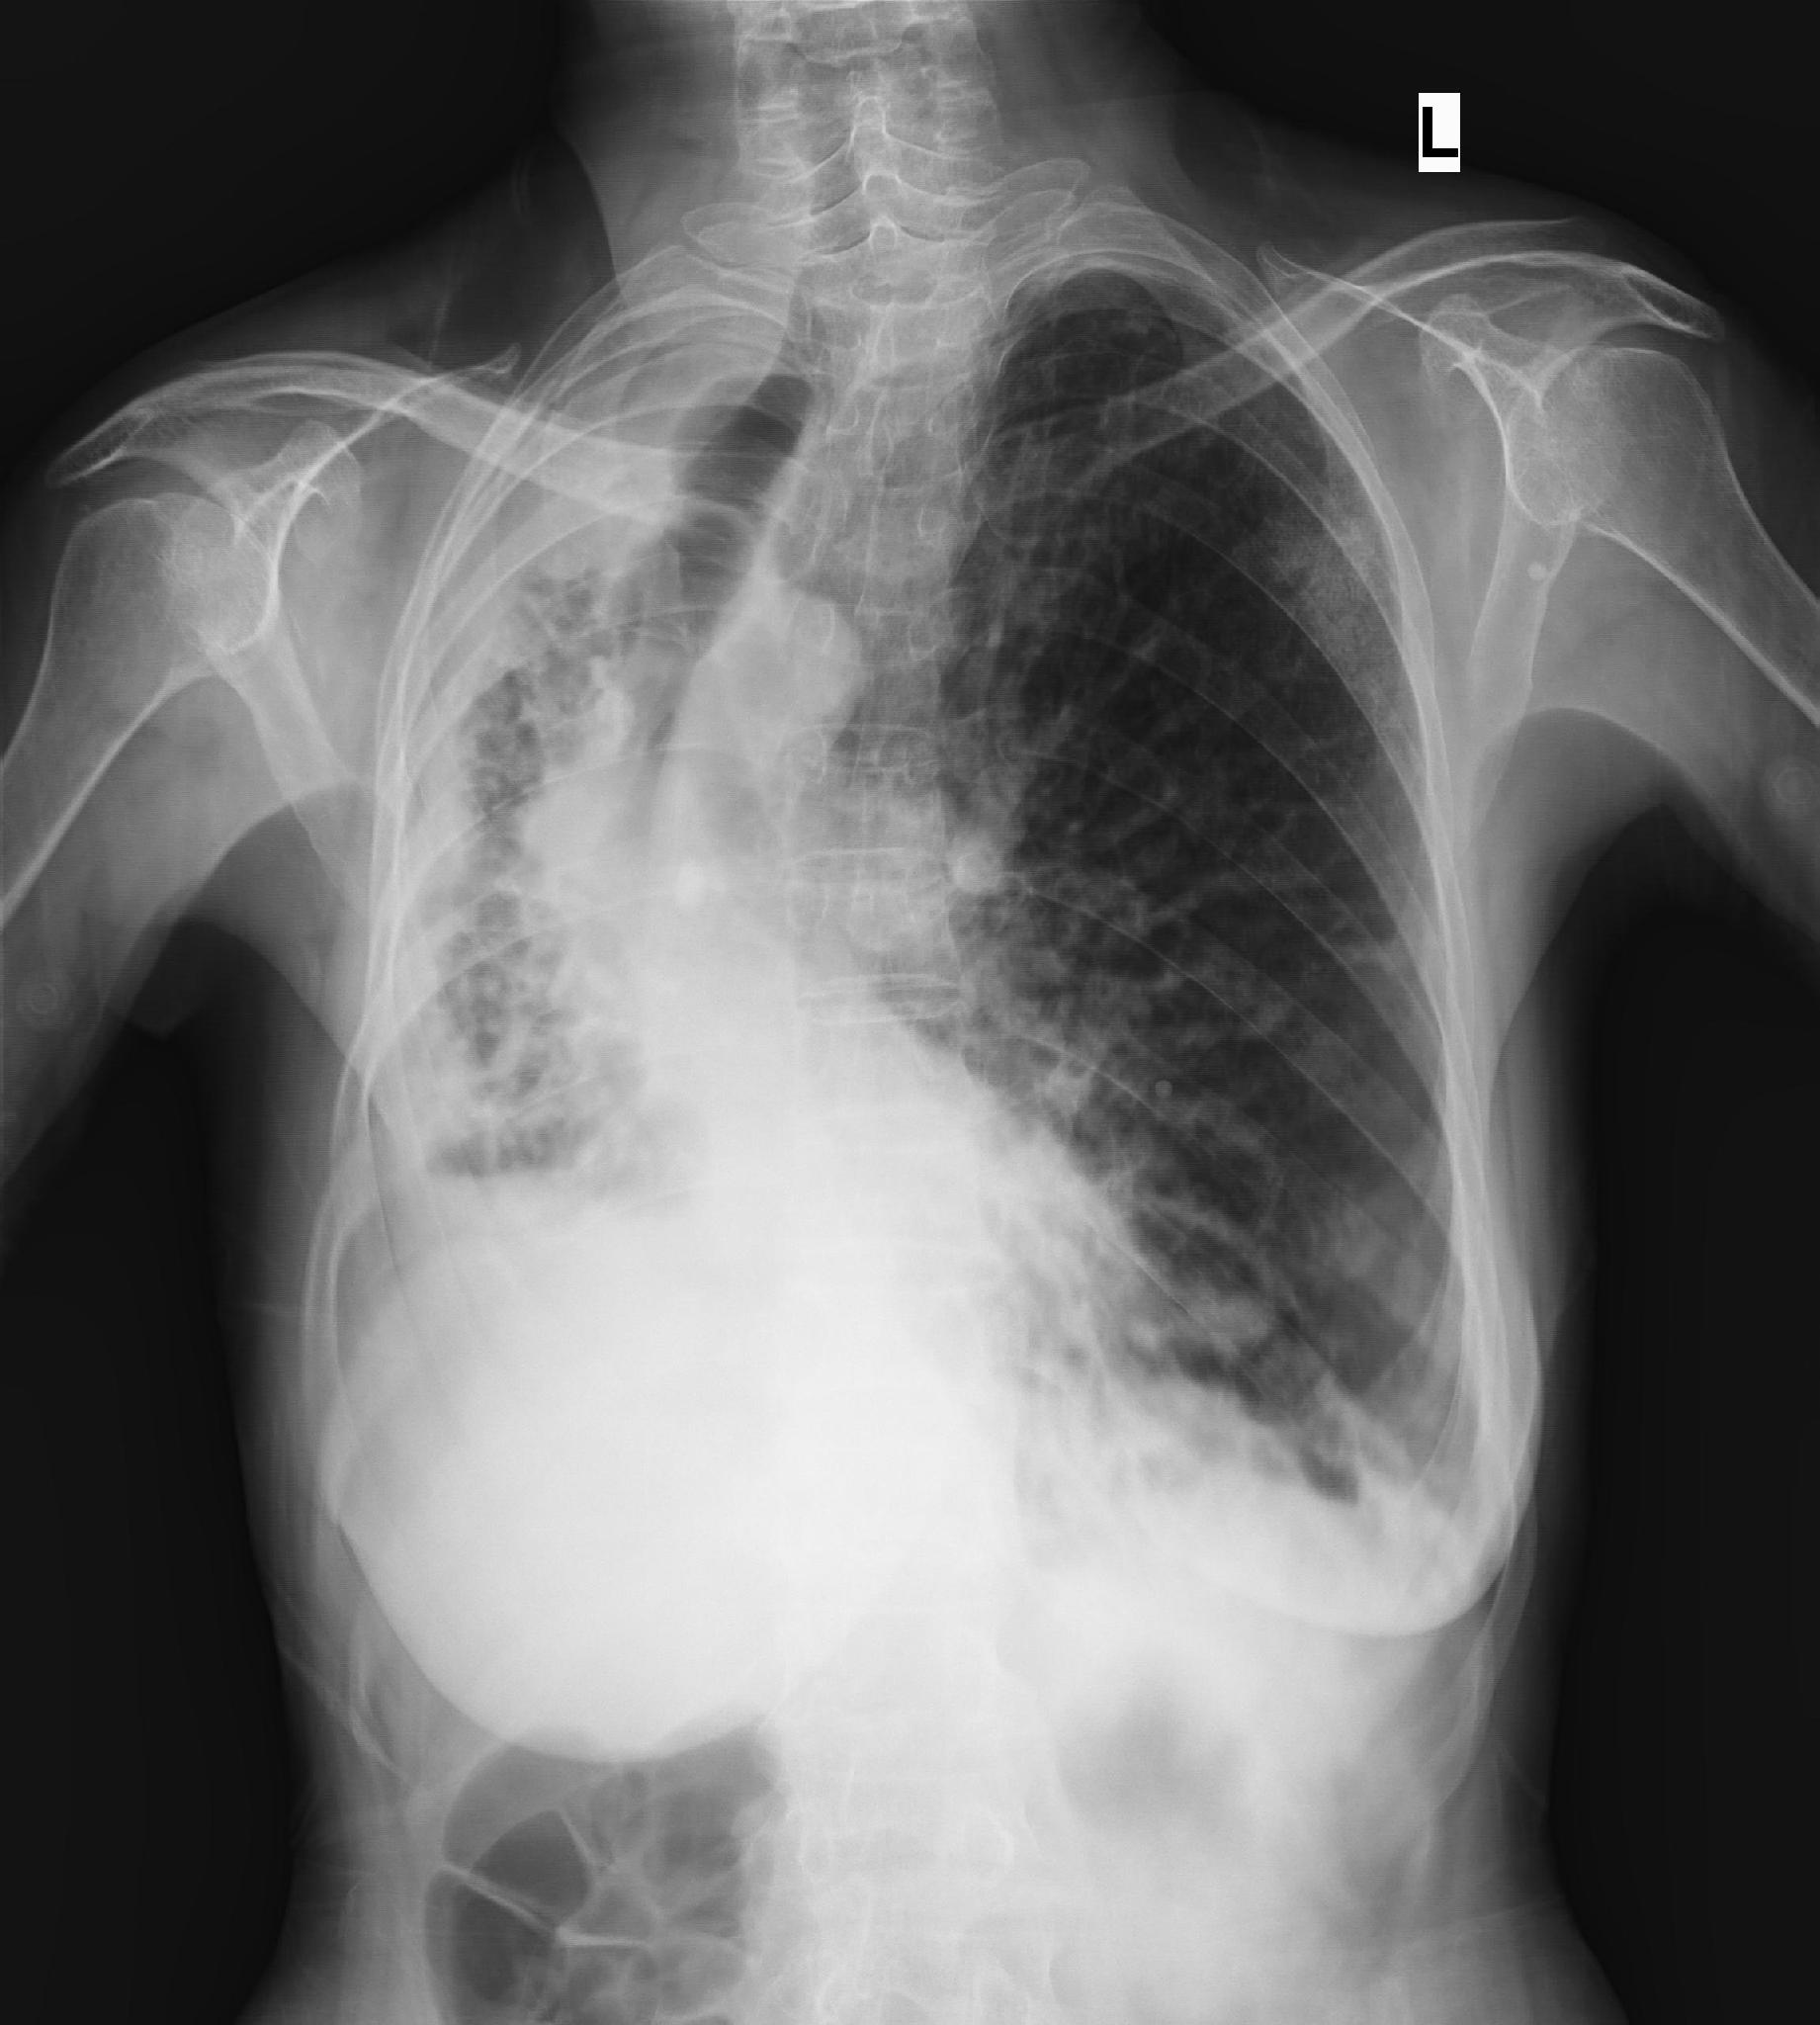

_左下肺肺纖維化病灶

_雙肺肺纖維化的

_雙肺肺纖維化肺灶